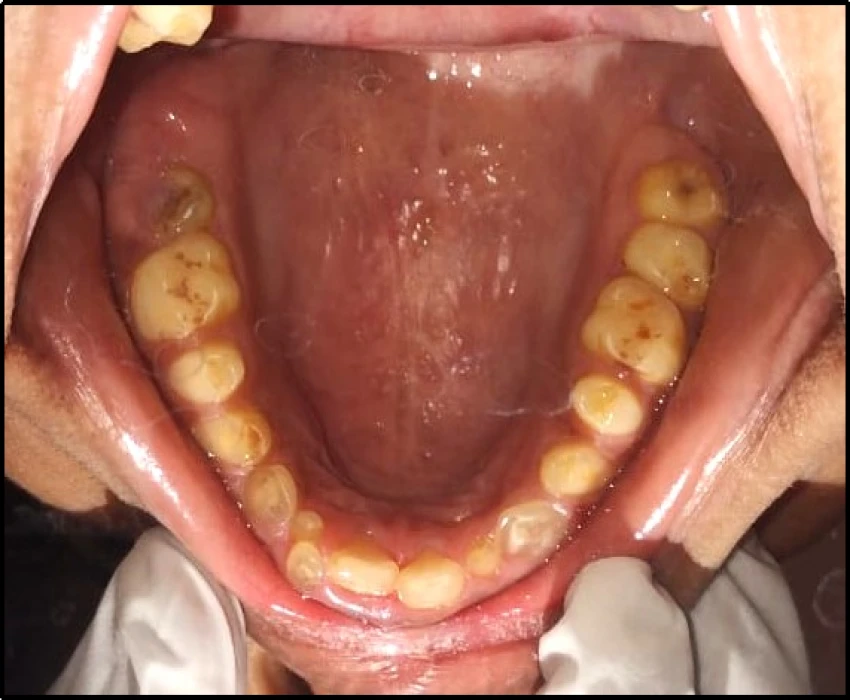

The patient came to the Department of Oral Medicine and complains of delayed eruption in lower front region of the jaw since 16 yr and irregular size and shape of the teeth in maxillary and mandibular region of the jaw since eruption of the teeth.

On intra-oral examination generalized loss of cervico-occlusion height and colour of the teeth appeared opalescent and brown in colour.

On the basis of history, clinical examination, and radiographic investigation final diagnosis was given as Amelogenesis imperfecta- Hypoplastic Type.

Appropriate treatment for amelogenesis imperfecta is restoration of the esthetics and function of the affected teeth.